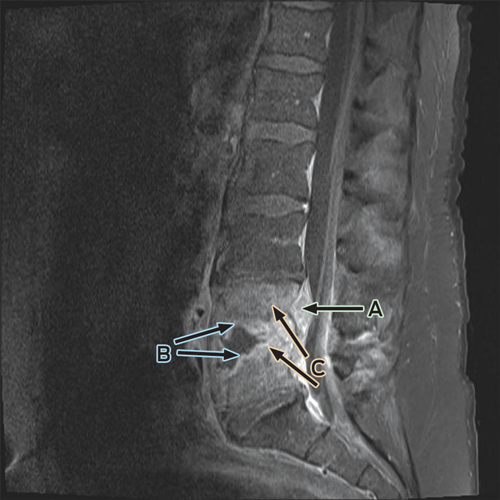

Despite ongoing cephazolin therapy, the patient developed increasing pain over the right sternoclavicular joint. Computed tomography imaging demonstrated changes consistent with a joint effusion, localised oedema, septic arthritis and osteomyelitis of the upper manubrium and medial right clavicle (Box 2). After initial conservative management without symptom resolution, surgical debridement was performed, and culture of the excised tissue grew MDR E. coli. The patient subsequently complained of lumbar back pain, and MRI of the lumbar spine showed changes consistent with an epidural abscess together with immediately adjacent discitis and osteomyelitis at the L4–5 vertebrae (Box 3). An orthopaedic consultation recommended conservative management, and the patient’s primary care was transferred to infectious diseases physicians. After 5 weeks of intravenous cephazolin therapy in hospital, he was discharged with a treatment regimen of intravenous ceftriaxone 2 g daily delivered by an elastomeric infusion device (Baxter) managed by the home-based acute care service.